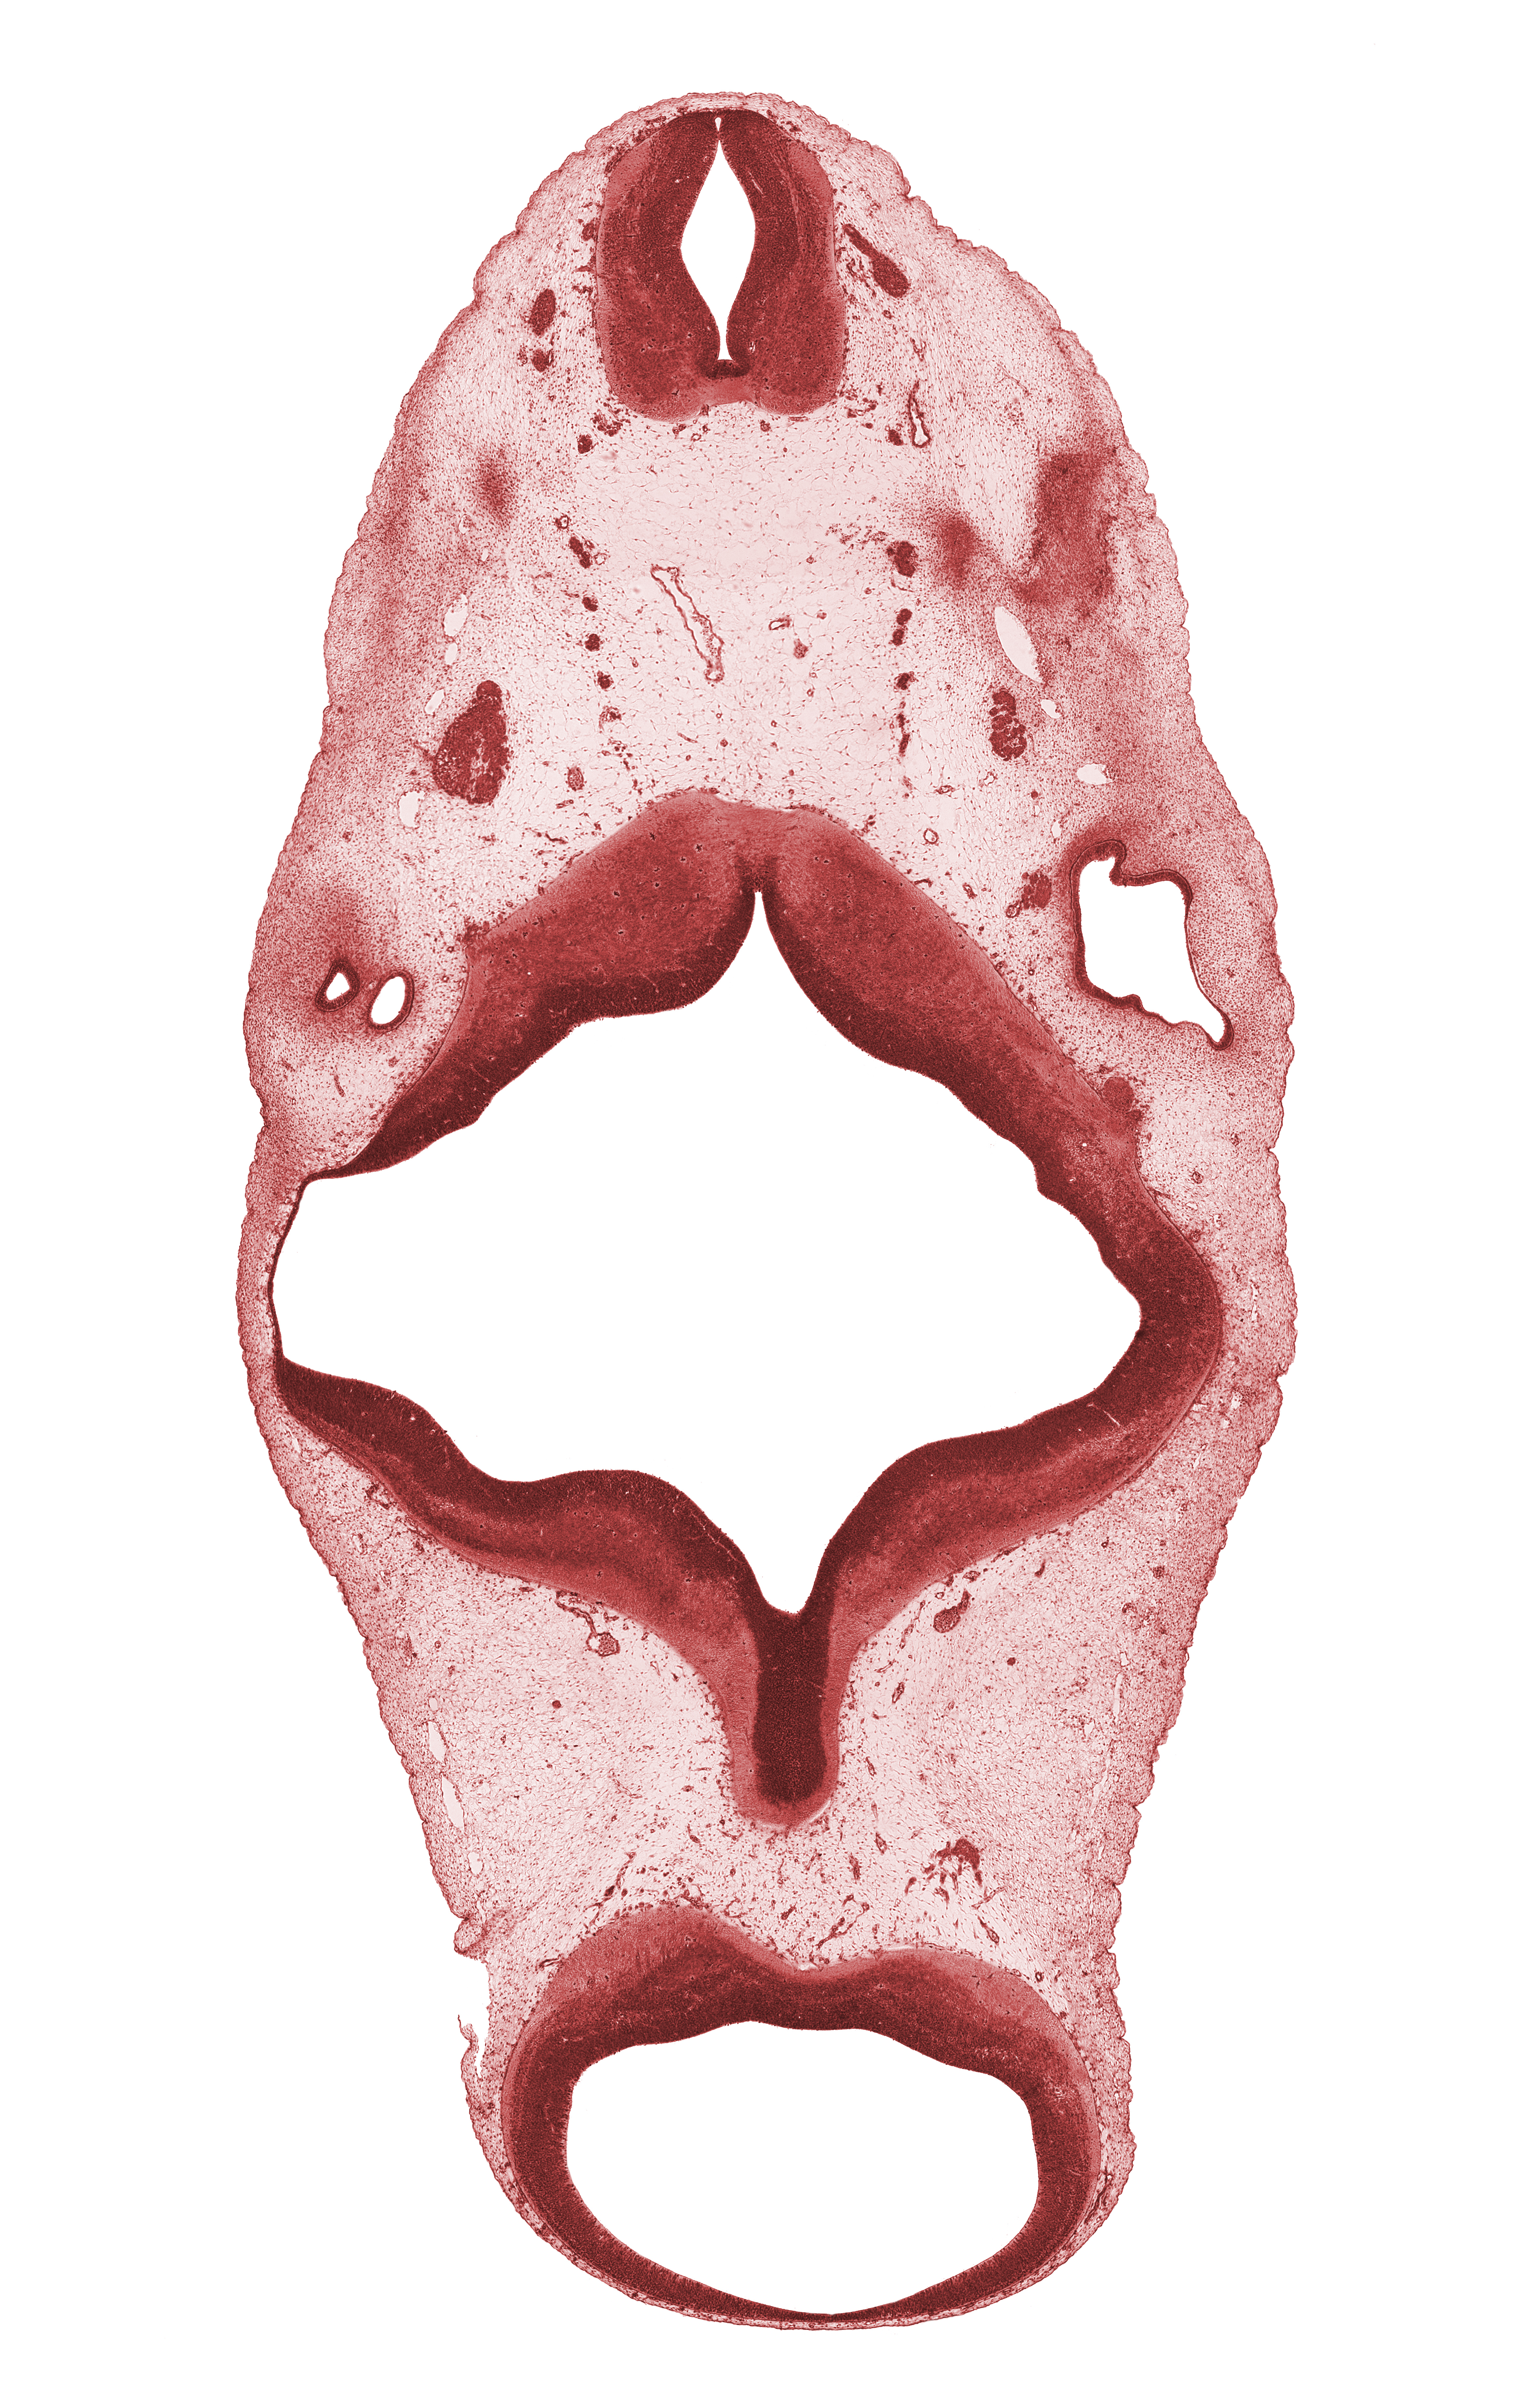

Carnegie Embryo #6520 | Location: 6-02-03

Keywords: C-1 spinal ganglion, anterior semicircular duct, central canal, oculomotor nerve (CN III), region of mesencephalic (cephalic) flexure, rhombomere 2, rhombomere 4, spinal accessory nerve (CN XI), vagus nerve (CN X), vertebral artery

Source: The Virtual Human Embryo.